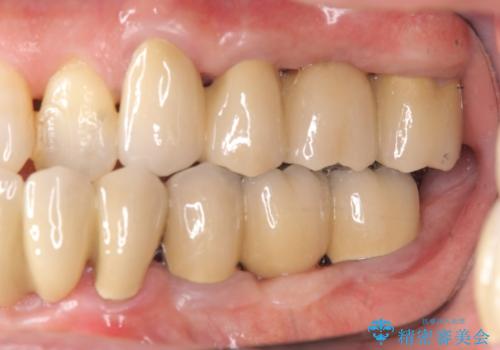

全顎的治療について

工程も多く、治療期間も長くなりがちですが、しっかりと通っていただいたおかげで安定した噛み合わせで食事を楽しむことができるようになりました。

メンテナンスも定期的に行うことで安定した状態を保っています。